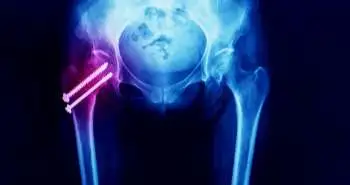

As per a study published in 'Journal of Orthopaedic Surgery and Research', the Fascia iliaca compartment block (FICB) could effectively reduce pain intensity up to 24 hours, total morphine consumption, and length of hospital stay in total hip arthroplasty (THA) patients. FICB is already known as an analgesic option for THA patients, although with a minimal amount of evidence.

The meta-analysis encompassed 8 RCTs. FICB significantly decreased VAS pain scores at 1–8 hours, 12 hours and 24 hours as compared to the placebo. Besides, the duration of hospital stay and the occurrence of nausea was significantly reduced in the FICB group compared to the control. VAS pain score at 48 hours and risk of fall was not improved in the FICB group compared to control.